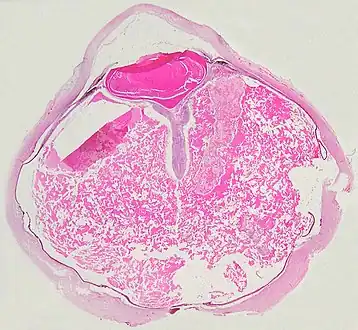

Pathology

Grossly, retinal detachment and yellowish subretinal exudate containing cholesterol crystals are commonly seen. Microscopically, the wall of retinal vessels may be thickened in some cases, while in other cases the wall may be thinned with irregular dilatation of the lumen.[10] The subretinal exudate consists of cholesterol crystals, macrophages laden with cholesterol and pigment, erythrocytes, and hemosiderin.[11] A granulomatous reaction, induced by the exudate, may be seen with the retina.[12] Portions of the retina may develop gliosis as a response to injury.

A case of Coats' disease, showing total exudative retinal detachment, and subretinal exudate containing cholesterol crystals (H&E)